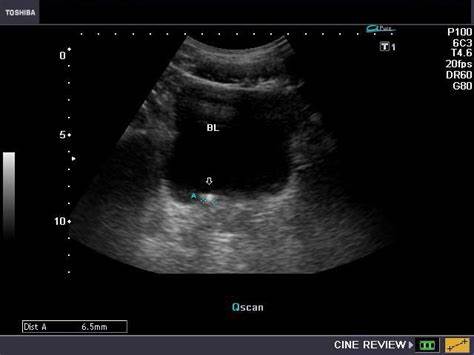

泌尿系结石

末端的输尿管结石会刺激膀胱三角区,刺激患者反复排尿。那么有人就要问了,为什么我不疼呢?结石梗阻以后,一般会引起急性疼痛,但是随着梗阻时间的延长,这种疼痛症状就会明显好转。同时老年人对于疼痛的耐受性较好,有的时候就会忽视掉这个问题。石头嵌顿在输尿管的末端,这个位置会刺激到我们的膀胱三角区,会刺激我们反复排尿,出现尿频尿急这些不同于典型输尿管结石的临床症状。

末端输尿管结石容易引起排尿症状